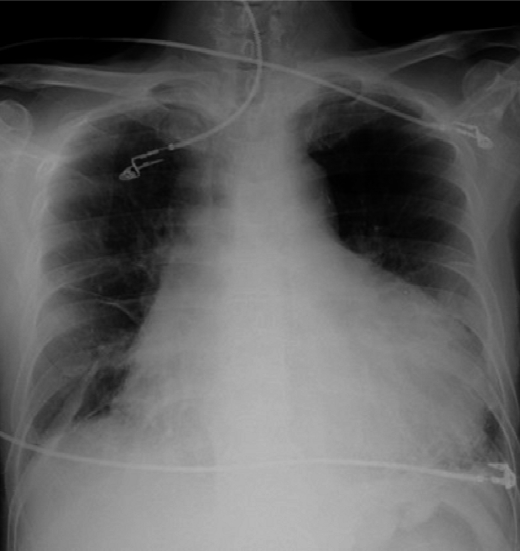

화이자 백신 부작용 심근염 및 심낭염

아나필락시스와 같이 화이자 백신 부작용으로 꼽히는 부작용은 심근염과 심낭염 모두 심장과 관련된 증상입니다. 간략하게 말하자면 심근염은, 심장 근육에 염증이 생겨 심장으로 정상적으로 혈액을 공급하지 못하는 증상이며, 심낭염은 심장을 둘러싼 판막 즉, 심낭의 염증으로 인해 통증이 생기는 증상입니다.

화이자 백신 부작용인 심근염과 심낭염은최근 12~17세 청소년을 대상으로 접종한 미국의 기록에 따르면 100만 명 당 약 13명으로 1차 접종 후 보다, 2차 접종 후의 경우가 더 높습니다. 보통 심근염 및 심낭염에 걸리면 특별한 치료 없이 호전되며 극심한 통증을 호소하는 분들 중 사망률은 약 2% 미만이라고 합니다.

대부분의 접종 대상자들은, 앞으로 해당될 것이기 때문에 관심을 가지고 지켜보는 것도 중요할 것 같습니다. 다행히, 심근염과 심낭염 증상의 대부분이 회복되고, 최소한의 치료만으로도 회복이 가능하며, 코로나에 감염되는 것보다 위험도가 현저히 낮다고 합니다.